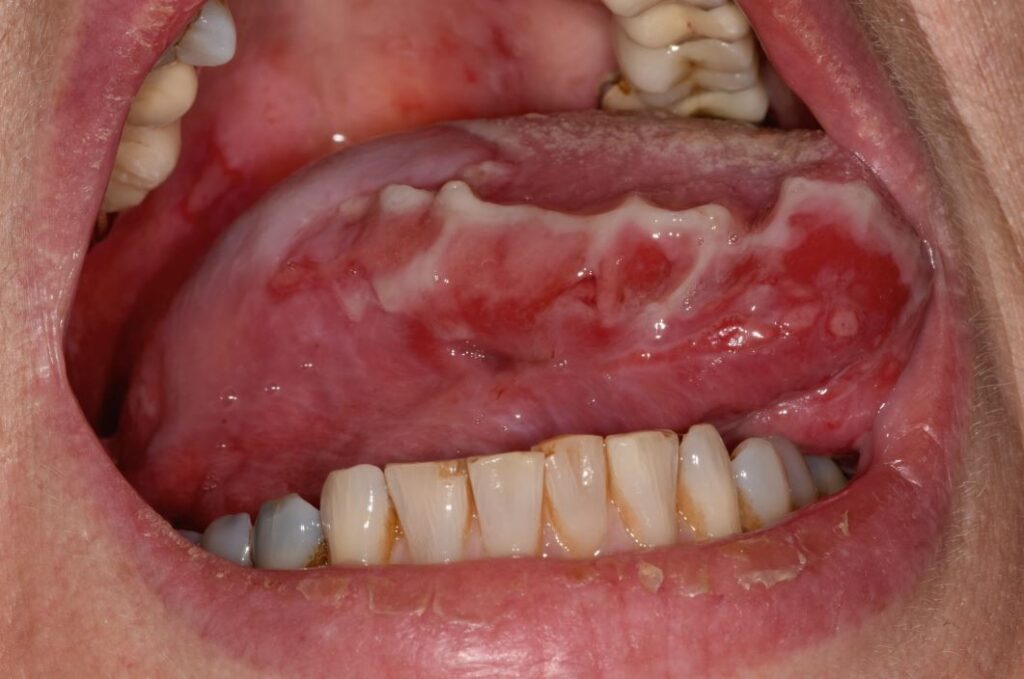

El enantema erosivo y doloroso es frecuente en pénfigo vulgar (PV) y puede preceder a las lesiones cutáneas entre 6 y 12 meses, afectando la alimentación y a veces retrasando el diagnóstico. Puede aparecer en mucosa oral, esófago, conjuntiva, mucosa nasal y genital, e incluso laringe.

. Pemphigus vegetans (PVeg): se reconoce por el patrón de giros y surcos en la lengua (“lengua cerebral”) y lesiones intertriginosas.

. Pénfigo paraneoplásico (PNP): estomatitis intratable y lesiones periorificiales graves.

El enantema de pénfigo: (a, b) Pénfigo vulgar (PV) (c). Pémphigo vegetans (Neumann) (d-f). Penfigo paraneoplásico (PNP).